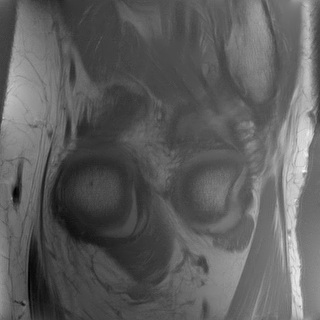

The elements in this family are good candidates for sampling densities: i) they are nearly constant and approximately equal to at the center of the k-space, ii) they can be anisotropic to accommodate for specific image orientations and iii) they have various decay rates, allowing sampling the high frequencies more or less densely. Some examples of such densities are displayed in Fig. 3(a). However, the family of densities generated by this procedure is quite poor. For instance, it is impossible to sample densely both the and axes simultaneously. In order to enrich it, we propose to consider the set of convex combinations of these elementary densities. This allows us to construct more general multi-modal densities, see Fig. 3(b) for examples of such convex combinations.

In order to construct the family , we first draw a large family of densities . They are generated at random by uniform draws of the parameters inside a box. We then perform a principal component analysis (PCA) on this family to generate some eigen-elements . We set . Since probability densities must sum to , we orthogonalize the family with respect to the vector . Thereby, we obtain a second family that satisfies and for all . This procedure discards one dimension. The resulting PCA basis is illustrated in Fig. 3(c).

As illustrated in Fig. 3(b), this process overall provides a rather rich and natural family. In practice, we select a value , so that the tail of the singular values contains less than of the energy. This value is also a compromise between numerical complexity (the higher , the more complex) and the richness of the family of densities that can be generated.